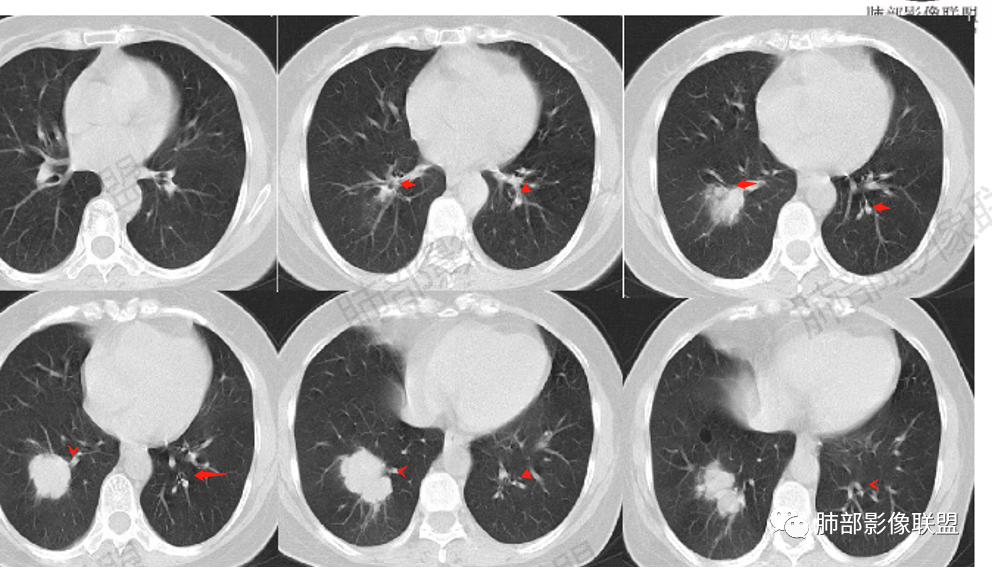

中年女性,既往直肠癌手术病史,现发现右肺下叶肿块,似两个结节融合。边缘膨隆,支气管阻塞,增强扫描不均匀强化,内血管影边缘模糊。考虑气道转移性肿瘤,鉴别肺原发肿瘤。

空格: 中年女性,结肠术后3年,转移的高发时段。胸部无症状,有肿瘤偷袭风险。影像特点。1 感觉不是一个结节(蘑菇兄弟?),有强化的分隔,血行转移单克隆膨胀生长应该可以排除。2 病灶有沿支气管扇形分布,有沿支气管生长的可能,有结肠癌支气管内膜转移的可能   3 病灶低强化,有坏死,结肠癌转移一般强化较明显。不知道病人术后有没有放化疗,引起的低免疫状态,是否存在机会感染的可能。支气管内膜转移的发生率极低,从概率的角度。我的排序:鳞癌》隐球菌(结核)》支气管内膜转移。

△外后基底段支气管应该堵了,深分叶,

就肺部病灶本身而言,深分叶,近端支气管显示欠佳,双侧对比还是符合堵塞,强化也支持恶性特点,那就是良性肿瘤不支持,如果要考虑良性,就是特异性感染了。

1.血道转移,落脚于血管末梢的肺间质,常两肺多发,随机分布,较少造成支气管阻塞,也很少见支气管穿行,罕见出现肺不张或阻塞性肺炎。

换句话说,如多个结节影与支气管关系密切,则较少会想到转移灶。

2.膨胀性生长,病灶往往较圆隆,如类圆形,边缘截然孤悬,似与相邻肺组织了无瓜葛!

3.结节影缺乏张力,或者收缩乏力,鲜有观察到毛刺。在孤立病灶,这都是与肺腺癌明显不同的。